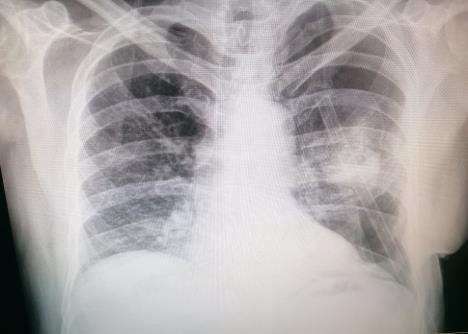

- Opcije su bile ili da se čeka ili da se operiše opet. S obzirom da nisam hteo ništa od ponuđenog, probao sam matoru metodu i jeftinu - da mu ubrzigam njegovu krv u grudni koš ne bih li uspeo da tako da mu zapušim rupu... Eksperiment je uspeo, rupa se zatvorila tokom 48 sati i pacijent se polako sprema za otpust kući, oporavljen... Živele knjige i hvala dragom Bogu na njima.